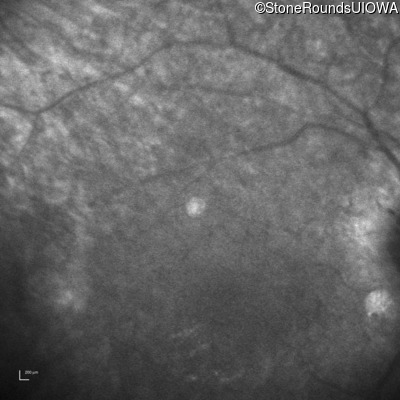

Infrared Fundus Photograph - Left -

No Light Perception

Exemplar

Expanded OCT Stack

×